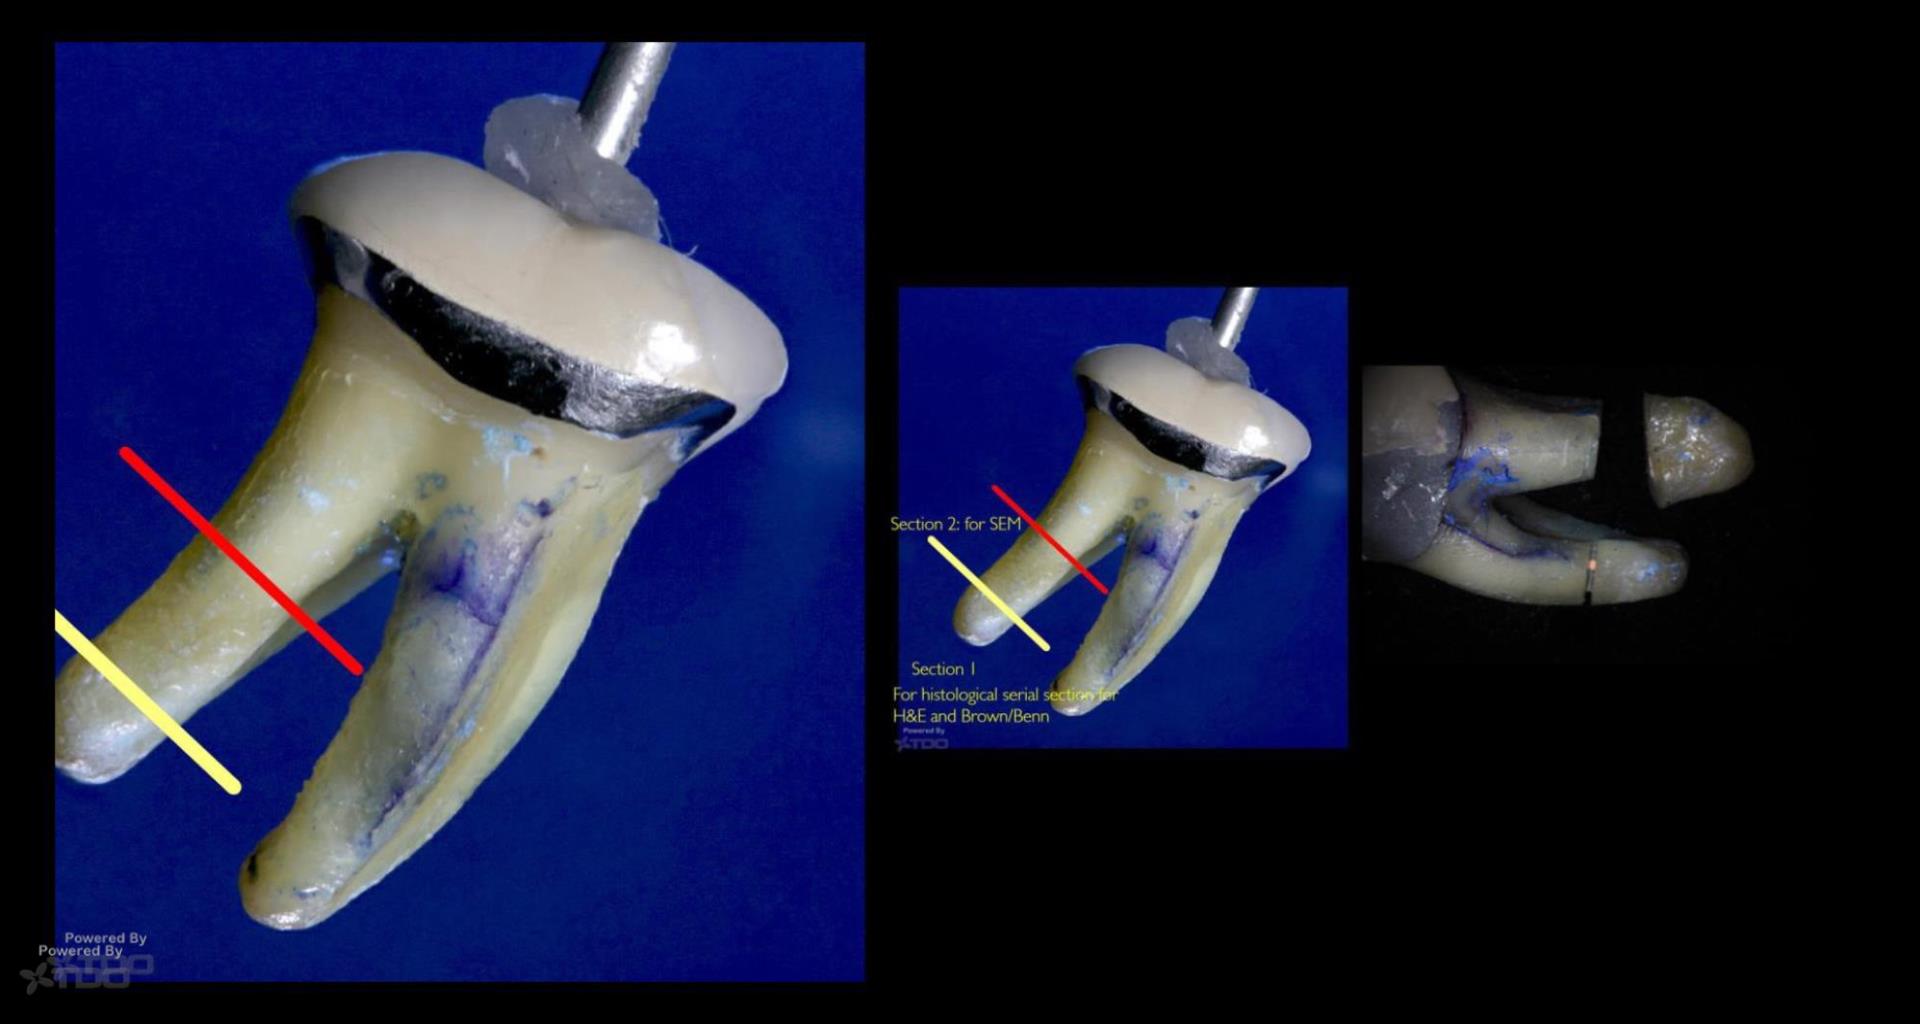

OK biofilm mavens…….I am ready to photograph the “Riccucci-style” processing of the apical distal root (#3)….. what do people think this will show? The same results Riccucci gets? Think before you answer….. gbc

Fascinating case! If you’re doing Ricucci-style processing on the apical distal root, I’d expect to see similar patterns of biofilm penetration—especially if there was a history of chronic infection.